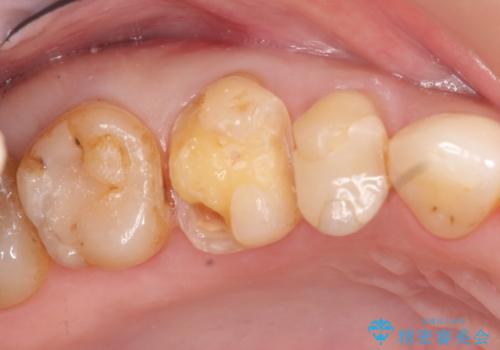

テトラサイクリン歯といって縞模様の強い歯の色調再現を行いました。

まず保険治療でコンポジットレジン修復を行い、神経の状態を確認した後、クラウンによる修復を行いました。